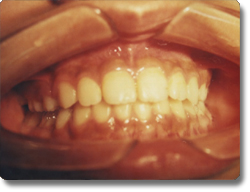

对于儿童及成人的牙齿排列不及,采用方丝弓固定矫正技术治疗儿童及成人的各类牙齿不齐。对于替牙期及恒牙牙列早期的骨性Ⅲ类错颌即“地包天”,采用固定快速扩弓,同期应用面具式前方牵引器,牵上颌前移,对牙面畸形进行矫形治疗,不仅治疗牙列不齐,同时矫正面部畸形,促使面部正常生长发育。